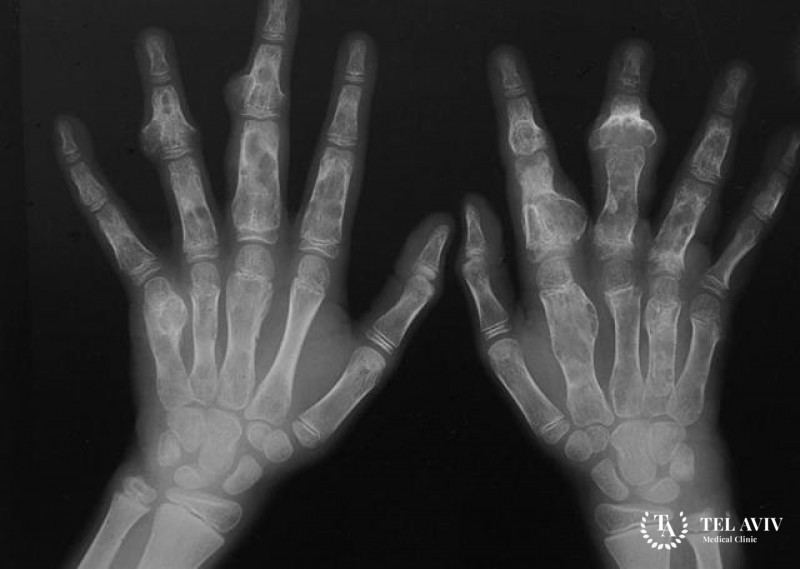

- Энхондрома располагается внутри костей, провоцируя их деформацию, хрупкость и ломкость, и отмечается склонностью перерождаться в злокачественную форму.